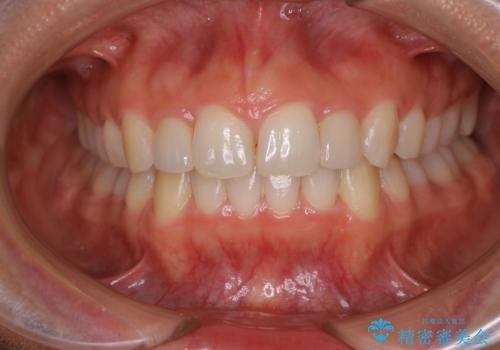

歯科技工士さんとの打ち合わせを重ね、周囲の歯としっかりなじむ天然歯のような被せ物をお作りすることが出来ました。

矯正治療と補綴治療をうまく組み合わせることで、美しい口元に仕上げることが出来ました。矯正治療、補綴治療をまとめて行える総合歯科治療を体現した治療といえます。